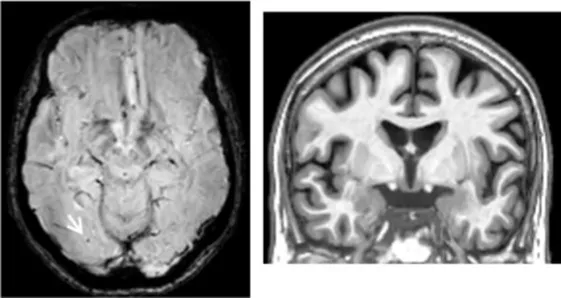

| Clinical findings | CSF and APOE | SWI and T1-weighted MRI scans | Proposition of ongoing neuroinflammatory processes |

| Case 21: a 59 y.o. woman with early onset symptoms and familial history of AD. At screening, she had 23/30 MMSE and impairment on episodic memory, executive functions, processing speed and categorical verbal fluency tests. Three lobar microbleeds, WMH (Fazekas’s score of 3/9) and moderate cortical atrophy were observed on MRI. | Aβ42: 462 P-tau: 140 T-tau: 768 APOE E3/E4 TSPO MAB | ![]() | ![]() Low cortical neuroinflammation compared to the cerebellar cortex. |

All fourth patients are right-handed. TSPO PET imaging showed SUVR relative to the cerebellar cortex and is represented in standard space in the same slice and intensity scale, whereas MRI scans are shown in native space. Cerebrospinal fluid AD biomarker values were abnormal for the four patients (see the method section for details).

Aβ42, amyloid-β 42; AD, Alzheimer’s disease; APOE, apolipoprotein E; CAA, cerebral amyloid angiopathy; CSF, cerebrospinal fluid; MMS, mini-mental state examination; MRI, magnetic resonance imaging, P-tau, phosphorylated tau; SWI, susceptibility-weighted imaging; T-tau, total-tau; TSPO, translocator protein; WB, whole brain; WMH, white matter hyperintensities.